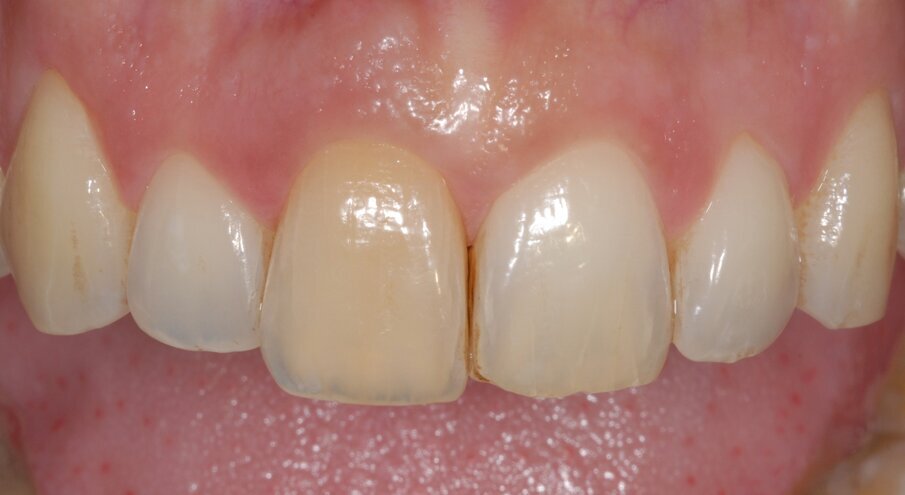

Alla paziente è stato chiesto di evitare di masticare sull’area trattata per 3 mesi e di evitare di lavarsi i denti per le prime 2 settimane. È stato prescritto un risciacquo con clorexidina allo 0,12% (Eburos, Dentsply) per 2 settimane. Successivamente, sono stati consentiti lo spazzolino convenzionale e il filo interdentale. La paziente ha mantenuto il provvisorio per 12 mesi, quindi è stata presa un’impronta, secondo la metodica di Hinds16 (Fig. 5). È stata, quindi, realizzata e avvitata sull’impianto una corona in zirconia-ceramica con moncone individualizzato (Figg. 6, 7).

Fig. 5 - I tessuti perimplantari a un anno dall’intervento sono molto belli sia per forma che per tono e stato di salute. Le papille sono competenti e la parabola è simmetrica a quella dell’elemento adiacente. La bozza radicolare è molto ben conservata (Root Bump Preservation RBP).